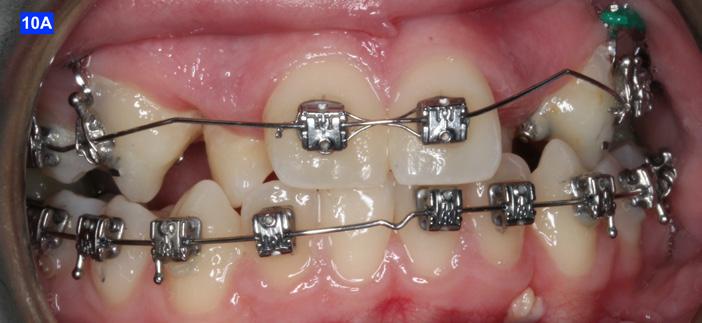

Finally, after 21 months of treatment, the patient and the parents consented to the odontectomy of the maxillary first bicuspids. The informed consent forms for the extractions and placement of TADs were signed by the parent, and all questions were answered. Risks, benefits, alternatives, and the result of no treatment at all were reviewed. Immediately after the odontectomy of #14(5) and #24(12), 1.6 x 8.0 mm AnchorPro (OrthoOrganizers) TADs were placed just mesially to the maxillary second bicuspids.6 In office power arms (a .018 x.025 SS) were fabricated and bonded to the buccal surface of the maxillary cuspids, just above the bracket.7 The purpose of the power arm is to place the applied force as close to the center of resistance of the tooth as possible. In this manner the line of action (power hook to the TAD) is parallel to the occlusal plane. The source of the force is an EC, and it must be replaced at least bi-weekly. Both arches had a .018 SS arch wire. There was a small off-center bend (tip-back, gable bend) “V” pointing occlusally, mesial to the maxillary second bicuspids.8 The purpose of this bend is to keep the roots parallel during the translation of the cuspids. There was a small OCS between #21(9) and #23(11) to shift the maxillary midline to the right. Another OCS was placed between #32(23) and #34(21) to facilitate the alignment of the mandibular left cuspid (Figure 8-A, B, C, D).

To prevent a disto-lingual moment (rotation) of the maxillary cuspids we attached PC from the lingual button on the cuspids to the framework on the hyrax. The anterior portion of the Hyrax was cut off and the remaining portion served as a TP arch for posterior anchorage. At this point, we were 25 months into treatment (Figure 9-A, B, C, D). The hyrax was removed after 30 months of treatment.

placed between the maxillary central incisors and the cuspids, on a .018 ss arch wire.8 The purpose of this center bend is to move the roots apart. A side effect of this center bend is that the crowns have a tendency to move together. Therefore, an OCS was placed between the maxillary central incisors and the cuspids. (Figure 10 – A, B)

After the maxillary cuspids were in contact with the second bicuspids, we had to ascertain that there was adequate width in the inter-radicular space. A center bend - “V” pointing gingivally was

To protract the maxillary lateral incisors into the arch, the bite was opened using composite build-ups on the mandibular first molars. The protraction was started with a .012 ligature tie, and the resiliency of the arch wire created the labial movement of the lateral incisors (Figure 10 - C).

Figure 8A: TADs in situ, frontal view 8B: TAD in situ, right lateral view 8C: TAD in situ, left lateral view 8D: Power arms Figure 9A: Maxilla, occlusal view 9B: Maxilla, occlusal view 9C: Maxilla, occlusal view Figure 9D: After the removal of the Hyrax, occlusal view Figure 10A: Center bend “V” pointing gingivally Figure 10B: OCS between the cuspids and the central incisors Figure 10C: Composite build-ups on the mandibular first molars Figure 10D: Adrian “U” bend spring